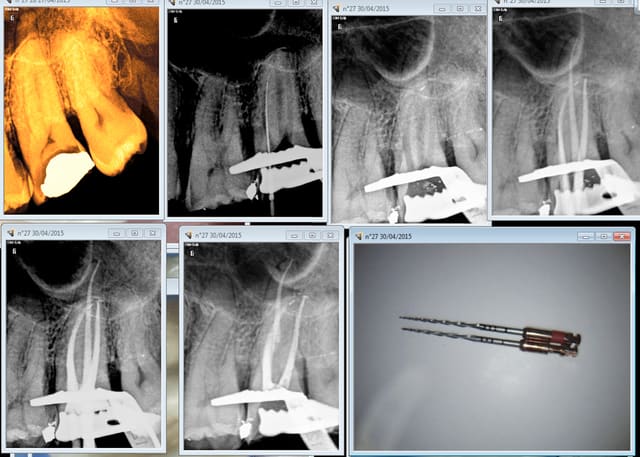

Tiens casa pour te faire plaisir. 1 mm de r25 pété sur cette 27. Quand on réutilise le matos censé ne servir qu'une fois pour cause de paiement au lance pierre du donneur d'ordre voilà ce qui arrive ( j'avais pourtant pris mes précautions (cathétérisme) sur cette dent de rhinocéros ultra longue)

Quelqu'un connait un endo exclusif pour aller chercher le morceau pété ? -))))